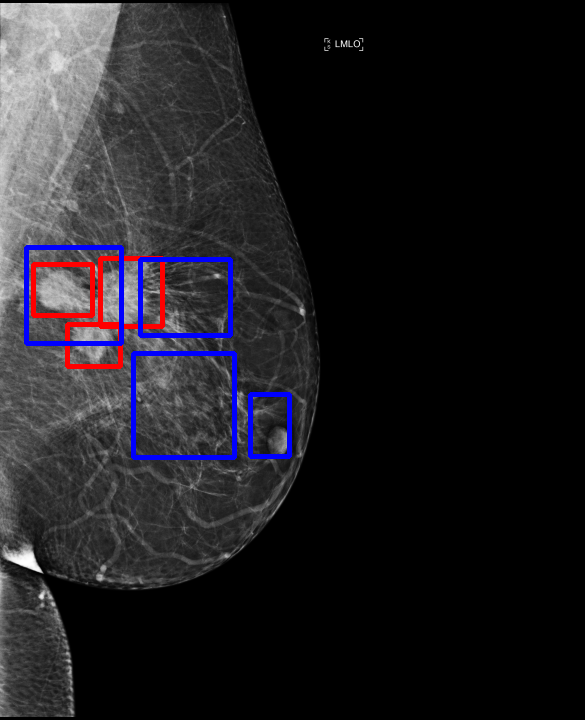

UDA has been extensively studied in case of natural images, utilizing techniques such as adversarial learning [21],pseudo-label training [6, 21, 40], image-to-image translation [40], graph reasoning [20], and adaptive mean Teacher training [6], improving domain adaptation efficiency of object detectors. Recently multiple works focused on using Mask autoencoders (MAE) methods in large-scale pretraining for vision models, involving masking parts of input and reconstructing them [12, 33]. However, these approaches overlook domain shifts. Alternatively, widespread utilization of Teacher-Student models, wherein a Teacher provides pseudo-labels for target domain (unlabeled images) to supervise a Student model, leads to notable adaptation improvements [40, 43]. However, these techniques face the challenge of incorrect predictions and excessive false positives per image due to low-quality pseudo-labels, particularly for medical imaging problems. Pseudo-labels are filtered from the Teacher model’s outputs based on the confidence score threshold. Selecting numerous pseudo-labels with low thresholds leads to inclusion of incorrect predictions, and compromising performance. Conversely, higher thresholds yield a limited number of pseudo-boxes, resulting in sub-optimal supervision. Existing Teacher-Student models often produce pseudo-labels riddled with errors and false positives, as illustrated in Fig. 1(a) and Fig. 1(b). Though [21, 40, 43] utilize techniques like adversarial alignment, weak-strong augmentation, and selective retraining of Student model to minimize the false positives in pseudo-labels, these approaches fail on medical images.

Contributions of this work. We note that screening mammography inherently differs from natural images, with breast abnormalities such as masses, asymmetries, and micro-calcifications, typically much smaller in comparison to the salient objects present in natural images, emphasizing the need for approaches specific to this problem. To address these issues, we make following contributions in this work: (1) We introduce D-MASTER, a transformer-based Domain-invariant Mask Annealed Student Teacher Autoencoder Framework for cross-domain breast cancer detection from mammograms (BCDM), integrating a novel mask-annealing technique and adaptive confidence refinement module. Unlike pretraining with mask autoencoders (MAEs) [12], leveraging massive datasets for training and then fine-tuning on smaller datasets, we present a novel learnable masking technique for the MAE branch that generates masks of different complexities, which are reconstructed by the DefDETR [44] encoder and decoder. Our approach, as a self-supervised task on target images, enables the encoder to acquire domain-invariant features and learn better target representations as shown in Fig. 1(c). (2) In Teacher-Student model, since the pseudo-label noise generated by the Teacher affects the Student model severely, we propose an adaptive confidence refinement module that progressively restricts the confidence metric for pseudo-label filtering. During the initial adaptation phase, soft confidence is applied allowing more pseudo-labels to learn better target representations. Subsequently, as confidence gradually increases, the focus shifts towards enhancing detection accuracy by prioritizing more reliable pseudo-labels. (3) We release a bounding box annotated subset of 1000 mammograms from the RSNA Breast Screening Dataset (referred to as RSNA-BSD1K) to support further research in BCDM. (4) We setup a new state-of-the-art (SOTA) in detection accuracy for UDA settings. We report a sensitivity of 0.74 on INBreast [25] and 0.51 on DDSM [18] at 0.3 FPI, compared to 0.61 and 0.44 using current SOTA respectively. Significant performance gains are also observed on our in-house and RSNA-BSD1K datasets.